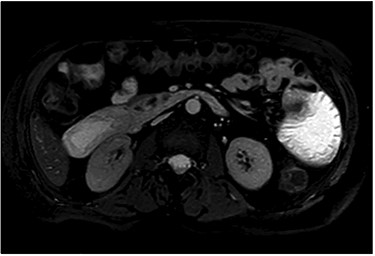

After clinical evaluation, the patient underwent computed tomography (CT) of abdomen and pelvis with IV contrast, which revealed fluid-filled esophagus, dilated stomach and first part of the small intestine with a transition point in the mid jejunum (Fig. 1). Her proximal small bowel, stomach and esophagus were significantly distended. She was subsequently decompressed with a nasogastric tube. For further delineation of this transition point, a magnetic resonance imaging (MRI) was performed, which confirmed a narrowed lumen secondary to an intrinsic mass of the jejunum (Fig. 2). Later, she underwent exploratory laparotomy with an evident transition point found at 30 cm from the ligament of Treitz (LT) (Fig. 3). We performed a partial small bowel resection and side-to-side stapled anastomosis. The rest of the bowel appeared healthy; there was no evidence of serosal involvement or extension to surrounding loops of bowel. Multiple enlarged lymph nodes were identified in the mesentery.

Stricturing lesion. The proximal small bowel was significantly dilated however, distally was viable and decompressed.